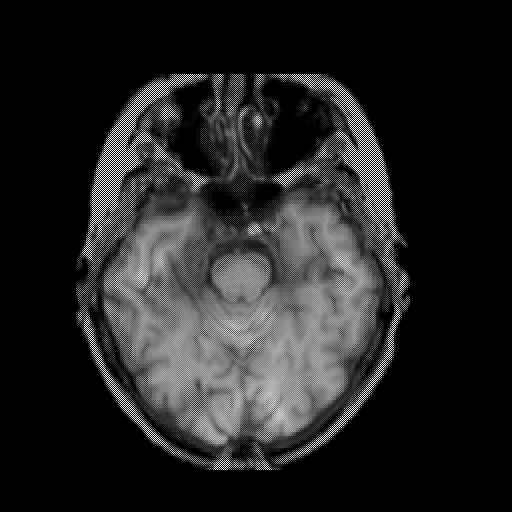

overlay: Slice 18

Slice 18

MRCBFCBF with

T1PDT2T1PDT2